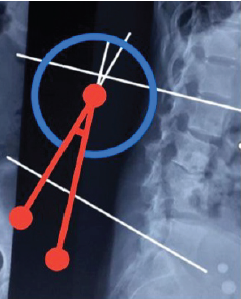

Posterior Decompression and Stabilization in Thoracic and Lumbar Spinal Tuberculosis: A Prospective Observational Study

Dharam Kabir Panthi , Vaibhav Jain , Yogesh Singh Parihar , Deependra Dubey , Suneet Tandon

………………………………p.405-413